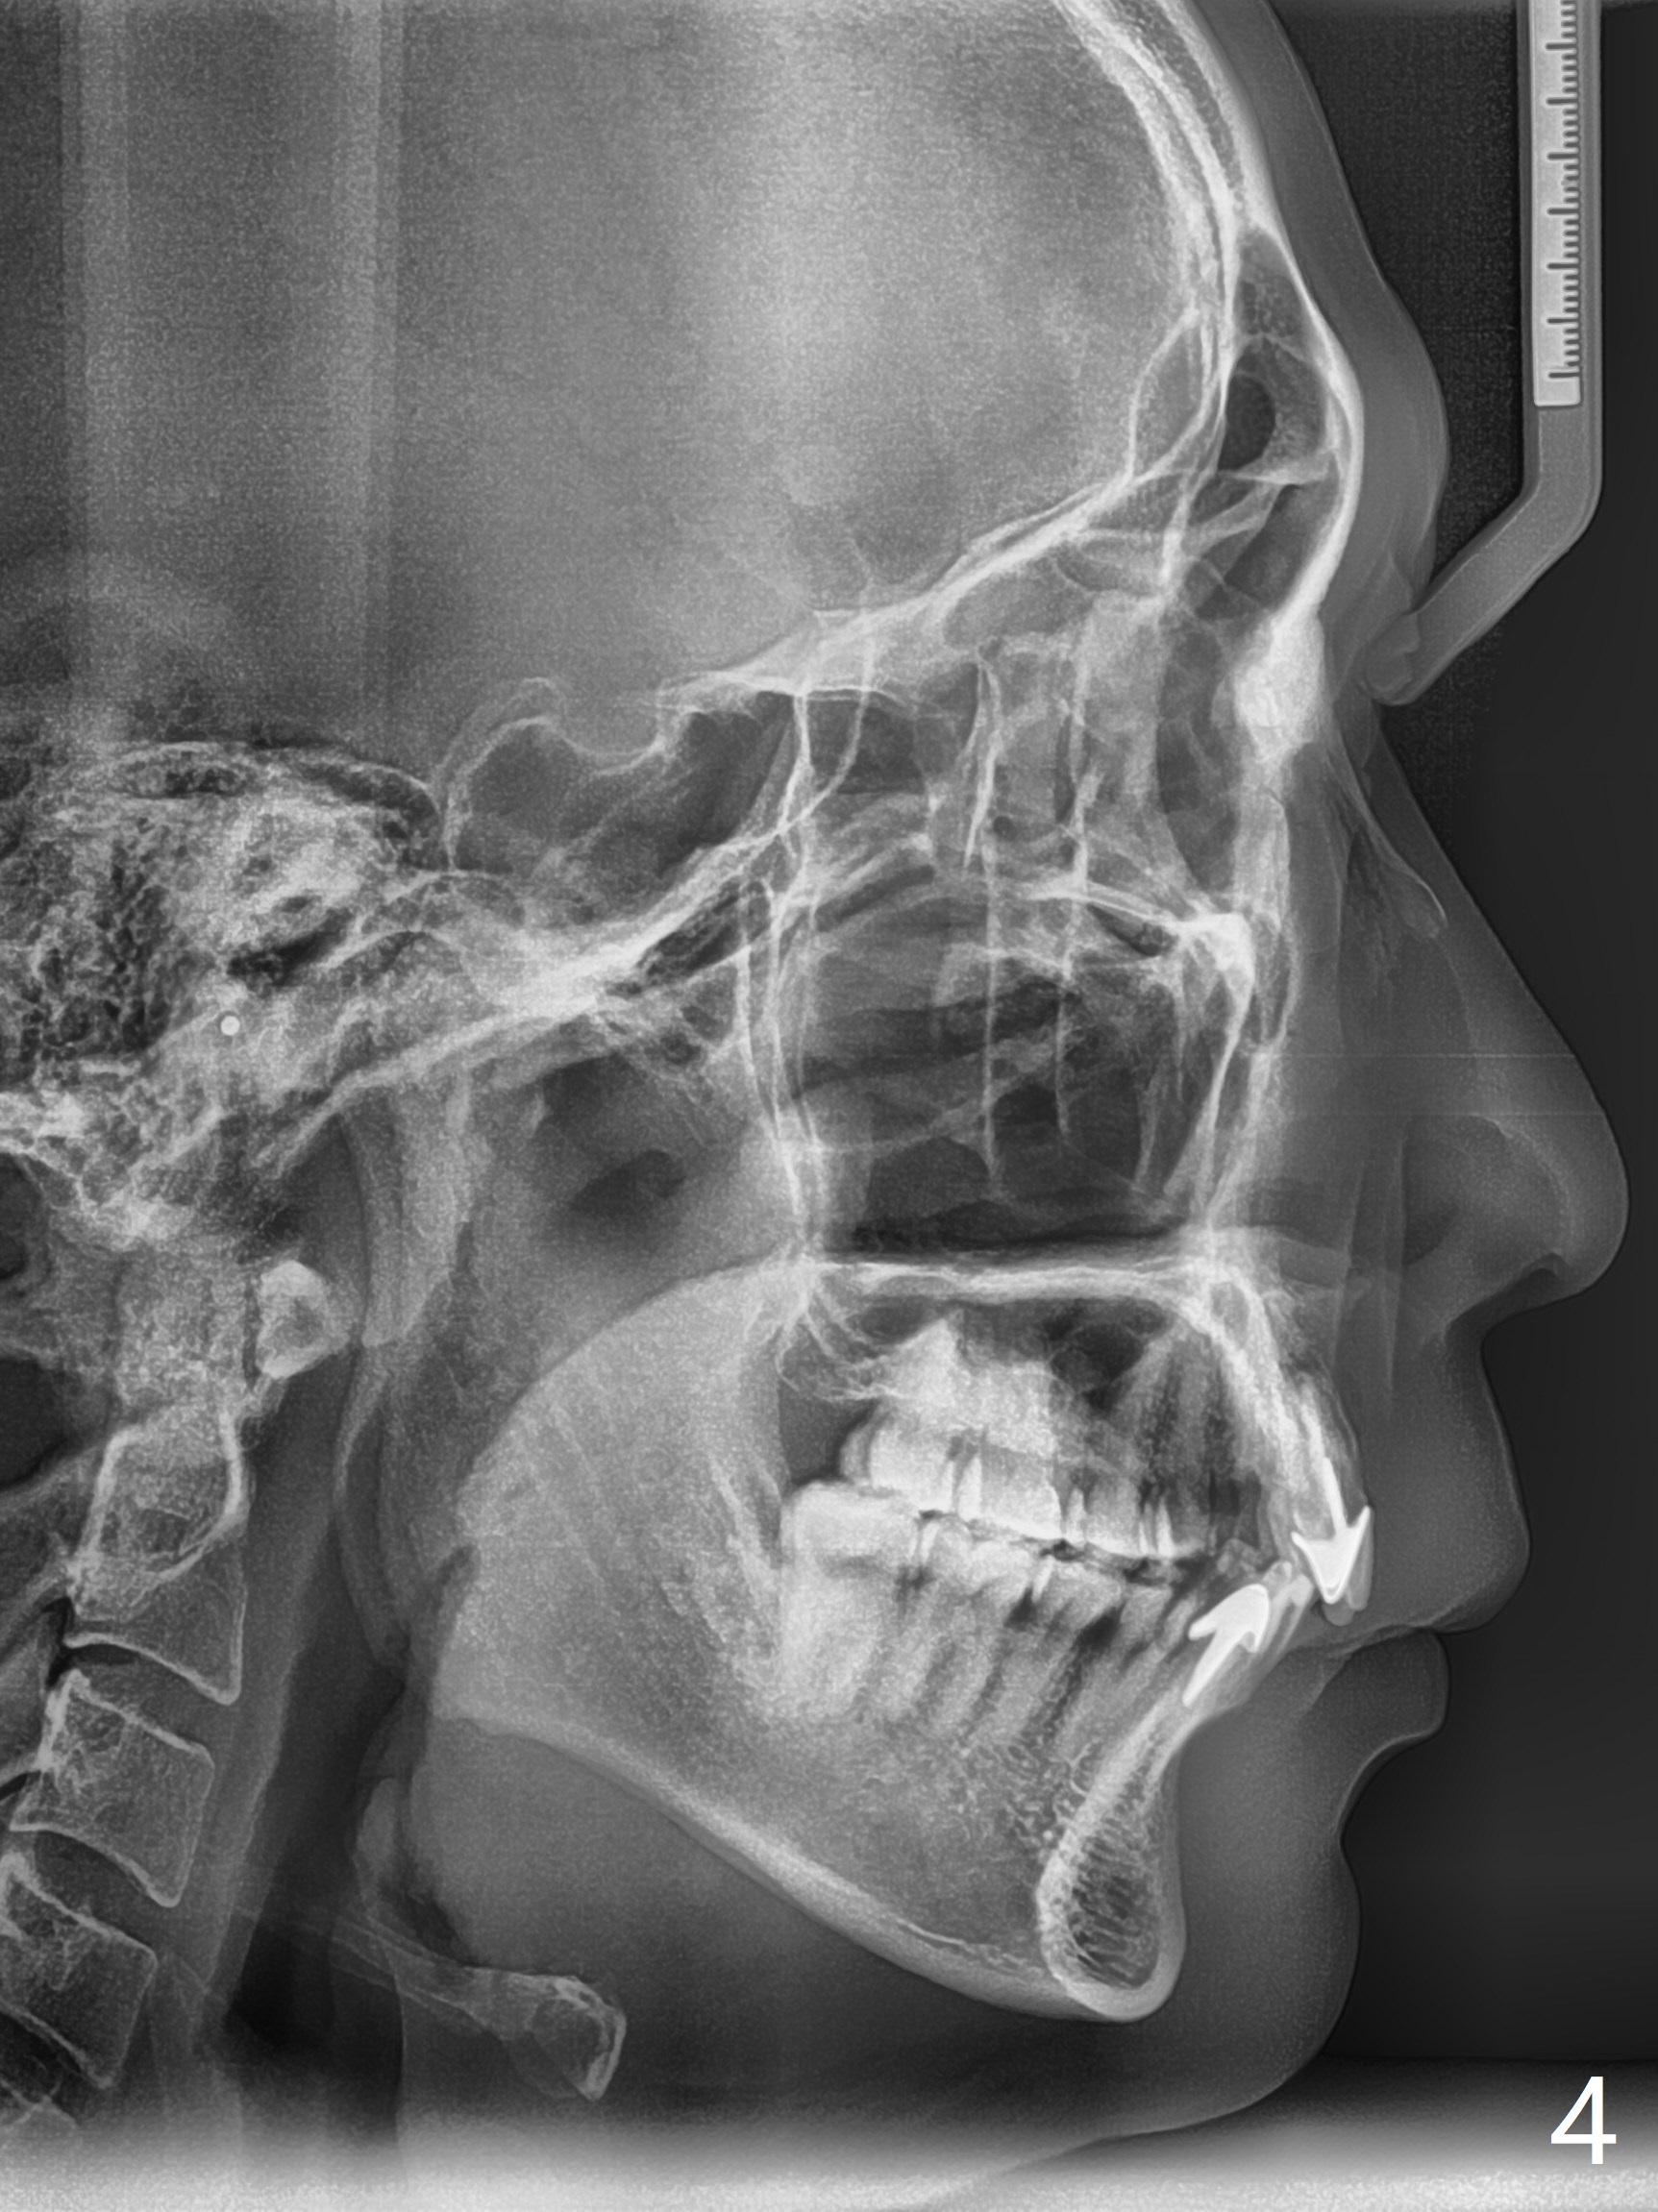

42岁男,小的时候做过矫正,据说智齿萌出后,畸形复发(图一至三)。临床检查显示:上前牙前突,下门牙拥挤,磨牙二类咬合。头颅侧位定位片证明Class II Division I Malocclusion (图四至六):SNA 84.63, SNB 76.11, ANB 8.52。 下周病人复诊,将拍摄照片,取模。正在考虑是否需要拍摄CT,排除上,下切牙是否位于牙槽骨唇侧,有利于做出拔牙决定。